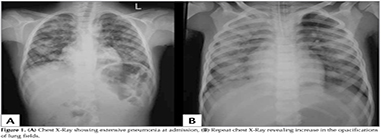

A 7-year-old previously healthy male presented with fever, cough without expectoration? since 7 days. He had recieved 2 days of co-amoxiclav tablets. There was no history of rash, sorethroat or ear discharge. On examination he was febrile (99.5?F), RR42/min, PR 96/minute and BP of 90/60 mm of Hg. Oxygen saturation at room air was 98%. There was no lymphadenopathy or conjunctival congestion. ENT examination was normal. Respiratory system examination revealed extensive crepitations all over the lung fields and bronchial breathing in the right interscapular area. Other systems examination was unremarkable. Investigations: -Hb 12.4 g/dL, TLC 7000/mm3, (Neutrophils 82%, Lymphocytes 16%), Platelet Count 2.81 lakhs/mm3 and ESR 35 mm. Chest X-Ray showed extensive pneumonia (Figure 1A]. His widal test, peripheral smear for malarial parasite, HIV serology and montoux test? were negative. He was started on Inj ceftriaxone and IV Linezolid. By 24 hours of admission child developed high degree fever (103?F) and severe respiratory distress (RR86/minute with chest retractions). Thinking of possibility of atypical pneumonia? started on azithromycin. Oxygen saturation was 90% at room air. Arterial blood gas analysis? showed a pH of 7.44, PCO2 of 30.4 mmHg, and PaO2 of 71 mmHg and HCO3 20. He was put on ventilator and after 2 hours he developed blood stained secretions from endotracheal tube. His TLC increased to 16940/mm3, neutrophils 90% and platelets 4.06 lakhs/mm3. His PT, aPTT and KFT were normal. His repeat chest X-Ray revealed increase in the opacifications of lung fields (Figure 1B). A nasopharyngeal swab for H1N1 viral testing and sputum for AFB, bacterial Gram stain and culture were obtained and started on oseltamivir along with IV meropenam. Pneumoslide-M test (Indirect immunofluorescence technique for IgM detection) which detects M. pneumoniae, L. pneumophila, Chlamidya pneumonia, Coxiella burnetii, Adenovirus, Respiratory Syncytial Virus, Influenza A,B, Parainfluenza (serotypes 1,2,3) done and was positive for M. pneumoniae. His urinary antigen detection for L. pneumophila was negative. Sputum gram stain showed gram-positive cocci in pairs and few gram negative bacilli and AFB stain was negative. Repeat arteial blood gases showed metabolic acidosis and PaO2 was decreasing. Gradually he developed septic shock features and started on inotropes. ECHO showed ejection fraction of 35%. Child was not maintaining oxygen saturation even with maximum ventilator support and repeat chest X-Ray showed deterioration of lung fields. Inspite of our efforts child could not be revived and declared dead within 48 hours of admission. His blood culture was sterile. TaqMan real time Polymerase chain reaction testing of nasopharyngeal swab specimen was positive for Swine influenza A H1N1 and negative for influenza B.

Figure 1A,B